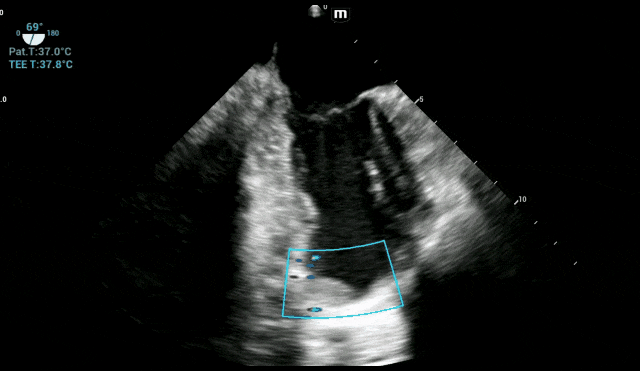

术中各时间段实时TEE监测心脏血栓情况

实时监控血栓的“一举一动”:全程动态观察左心室血栓的大小、形态、活动度及附着位置,及时发现血栓的细微变化,主要针对两类人群,一类是术前已存在血栓的患者,另一类是血栓高发人群。

手术关键操作期:TEE始终锁定左心室,确认血栓无任何移位或脱落迹象,为外科医生创造了安心操作的环境。